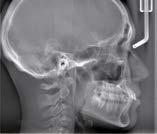

Partielle cephalometrische Aufnahmen

Die Bereiche, die für die Untersuchung nicht relevant sind, werden durch Ausblendung nicht bestrahlt. Es gibt drei partielle Aufnahmemodi für Ausblendungen, die die Röntgendosis reduzieren.